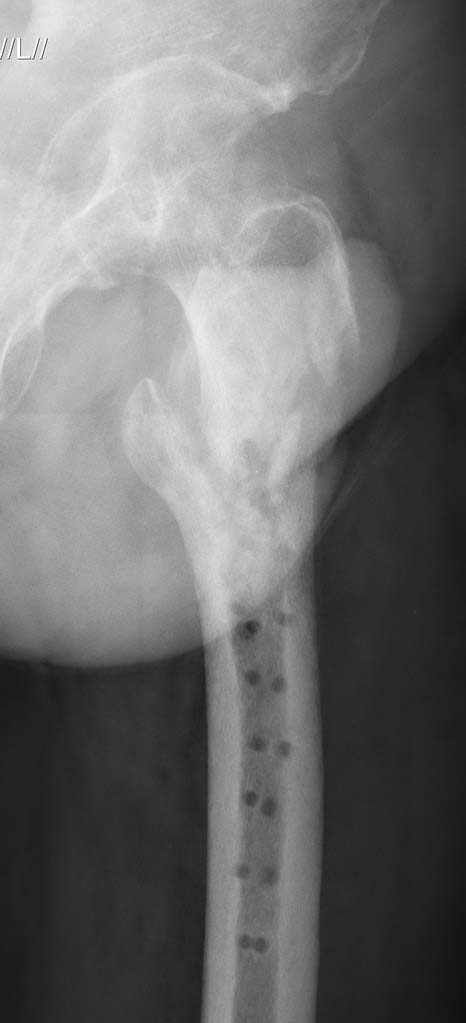

Вот еще снимки после и КТ.

Отсутствие привычной рентгенологической картины тазобедренного сустава тревожит. Похоже на результат коксита.

Сустава практически нет. Не вижу смысла пытаться делать реостеосинтез.

по картинке, действительно, похоже на результат коксита, однако можно думать и о выраженном остеопорозе, учитывая отсутствие опорной части головки стоит ли выполнять реостеосинтез?